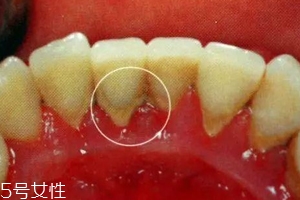

牙結(jié)石是不會(huì)自動(dòng)脫落的,因?yàn)樗卫蔚母街谘例X表面,當(dāng)然有時(shí)候會(huì)有極少數(shù)的牙結(jié)石會(huì)因?yàn)槟闼⒀阑蛘哂醚篮瀯兟洌皇菢O少數(shù)現(xiàn)象。所以有了牙結(jié)石千萬不能忽視,它不會(huì)像感冒一樣會(huì)自行康復(fù)的,它們只會(huì)在你的牙齒表面沉積下來,日積月累,使你的口腔患上炎癥,這樣只會(huì)導(dǎo)致牙齦炎癥逐漸加重,并發(fā)展為牙周炎,最終導(dǎo)致牙齒松動(dòng)脫落。不要奢求牙結(jié)石會(huì)自動(dòng)脫落了,請(qǐng)重視起來,為了你有一口健康的好牙!

牙結(jié)石第一階段:我們口腔并不是無菌的狀態(tài),口腔內(nèi)有無數(shù)個(gè)細(xì)菌,每當(dāng)我們吃飯食物,食物殘?jiān)诳谇豢p隙超過5分鐘之后就會(huì)形成牙菌斑(牙菌斑就是牙結(jié)石的幼年體)。而且,牙菌斑是粘附在牙齒表面的不易被沖走,這就給更多的細(xì)菌提供肥沃的土壤,一般來說,牙菌斑會(huì)在1-2h迅速增厚,10天之內(nèi)發(fā)展成熟達(dá)到高峰,所以我們應(yīng)當(dāng)在12h左右清除牙菌斑(牙刷,牙線)。

牙結(jié)石第二階段:細(xì)菌有了肥沃的土壤,便會(huì)呼朋喚友前來定居,這時(shí)候,如果你還不注意口腔衛(wèi)生,不及時(shí)清除食物殘?jiān)?,那么,牙菌斑和食物殘?jiān)鼤?huì)在「唾液」的侵泡下經(jīng)過24小時(shí)會(huì)被唾液中的成分「鈣化」,變成「初始」的牙結(jié)石啦。

牙結(jié)石第三階段:然而,牙結(jié)石并不是一成不變的,這種初始的牙結(jié)石會(huì)繼續(xù)沉積、礦化,越積越后,越積越硬,最后牙刷都拿它沒辦法,只能通過醫(yī)用器械將其清除。